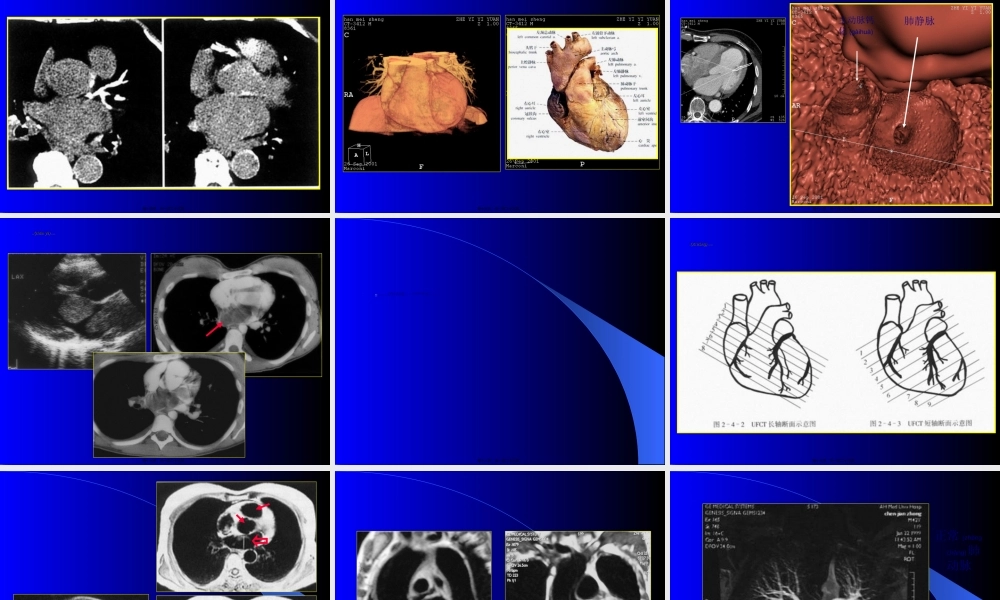

第二章心脏第二章心脏(xīnzàng)(xīnzàng)与大血管与大血管第一页,共一百二十九页。第二页,共一百二十九页。心脏大血管(xuèguǎn)的影像学检查方法有哪些?问题心脏(xīnzàng)大血管病变的基本X线表现是什么?怎样观察心脏的X线表现?了解各方法大致有哪些优缺点?常见病变的个性表现又是什么第三页,共一百二十九页。普通X线检查(jiǎnchá)心血管造影检查CT检查MRI检查USG检查放射性核素扫描一、检查方法第四页,共一百二十九页。(一)普通X线检查实时、动态、多角度地观察心脏大血管的外形及运动情况(qíngkuàng)。第五页,共一百二十九页。第六页,共一百二十九页。正常心脏大血管正常心脏大血管(xuèguǎn)(xuèguǎn)在胸腔内的方位横断向示意在胸腔内的方位横断向示意图图第七页,共一百二十九页。不同体位心脏大血管结构不同体位心脏大血管结构(jiégòu)(jiégòu)投影示意图投影示意图RRRR45°60°第八页,共一百二十九页。第九页,共一百二十九页。(二)CT检查常规CT扫描:作为断层扫描,用于检查心包病变、心脏大血管腔内病变、管壁病变以及纵隔内病变与心血管的关系。超速CT扫描:除上述用途外,尚可对心脏功能(如心肌运动、心肌重量、心搏出量、射血分数、心肌灌注状态等)进行定量分析。CT血管造影(CTA):通过造影剂的对比增强效果,应用先进(xiānjìn)的计算机软件对扫描范围内的血管进行重建并使之良好显示,常用于初步筛查。第十页,共一百二十九页。心电门控心电门控CTCT扫描定位扫描定位(dìngwèi)(dìngwèi)相,目的是使在同一心脏搏动点获取图像。相,目的是使在同一心脏搏动点获取图像。第十一页,共一百二十九页。CTCT增强扫描后心肌和心腔对比度增加,更好地显示增强扫描后心肌和心腔对比度增加,更好地显示(xiǎnshì)(xiǎnshì)心肌结构,同时可观察瓣膜及乳心肌结构,同时可观察瓣膜及乳头肌。头肌。第十二页,共一百二十九页。电子束电子束CTCT增强增强(zēngqiáng)(zēngqiáng)扫描后冠状动脉成像扫描后冠状动脉成像第十三页,共一百二十九页。冠状动脉冠状动脉(guānzhuàng-dòngmài)(guānzhuàng-dòngmài)粥样硬化(冠状动脉粥样硬化(冠状动脉(guānzhuàng-dòngmài)(guānzhuàng-dòngmài)钙化)钙化)第十四页,共一百二十九页。血管血管(xuèguǎn)(xuèguǎn)表面重建(前面及下面观)表面重建(前面及下面观)第十五页,共一百二十...